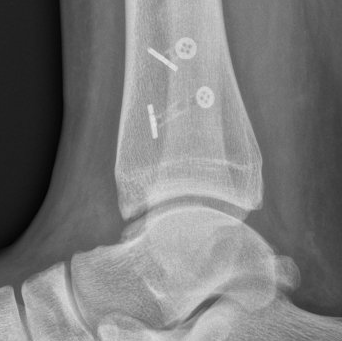

Unstable injuries treated within six weeks of injury require "keyhole surgery"

involving ankle arthroscopy and syndesmotic stabilisation using one or two TightRope or ZipTight

devices (see images below).

This is followed by progressive weight-bearing and a month in a "moon-boot" with physiotherapy-assisted rehabilitation.